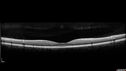

27 year old female 6 days ago she noticed she had a very bad headache and she was home trying to fix her makeup and she had the left eye closed and could not see out of the right eye. Since then she has pain behind the right eye. She has poor circulation and her hands sometimes fall asleep. In February she had a fever but did not see a doctor. (2 months ago) She had cold sweats throughout the night which lasted for just a few days. She started dating someone who has a cat for the past few months (they started seeing each other in January). She usually avoids cats because she is allergic. The cat had fleas.I have her tests which were done in the ER on two visits. Her MRI scan was negative (MS was a concern). Also, her blood work showed a slightly elevated white count with a neutropenia which was mild. The rest of her CMP and blood count was normal. Her urine catch was abnormal but had a normal culture. It had multiple epithelial cells. There were ketones and red cells in the urine. I'll have this rechecked and make sure she follows-up on the UA. VA OD: scCF 4ft PHNI NscUnable VA OS: sc20/25 NscJ1+ The right eye has disc edema and the left eye has retinitis - She was treated with Doxycycline 100 mg BID and vision returned to normal in a few months

Cat Scratch - Neuroretinitis OD AND retinitis OS - Bartonella henselae positive496 views27 year old female with exposure to cats and prior fever. Reports with recent vision loss right eye. She was treated with doxycycline and within 2 weeks the right eye looks better. Then she skipped all follow-up visits. The right eye presented 20/200 and the left 20/1600000